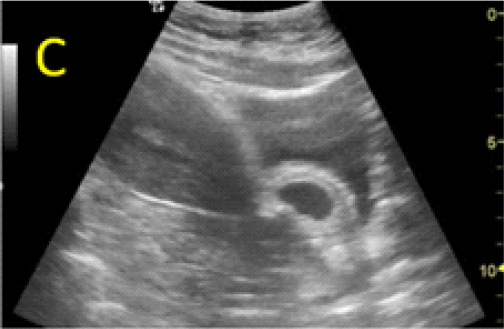

Figure 3 – Ultrasound evaluations on Day 3 (A, B) and 7 (C, D) after MTX administration, with B-hCG values of 103.016 and 57.710mUI/ml, respectively. Fetal growth and normal heart activity is present.

assessment revealed the persistence of embryonic cardiac activity and intense trophoblastic vascularization. HCG constantly decreased to 57,710mUI/ml on day 7 after MTX administration but the embryonic cardiac activity was still noted with a normal rate.